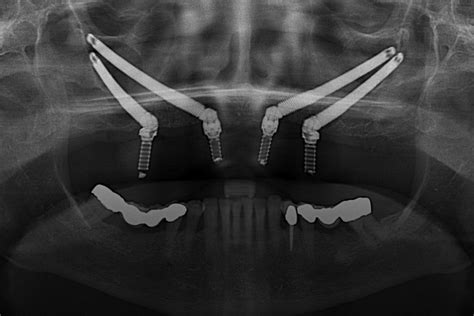

ANA MARÍA: Atrofia maxilar severa - Implantes cigomáticos y anteriores, regenereación ósea

- Implantes dentales cigomáticos: Los implantes cigomáticos son una alternativa ideal cuando no es posible realizar un injerto óseo en el maxilar superior. Los implantes cigomáticos son implantes dentales especiales que se anclan en el hueso cigomático, un hueso fuerte situado en la parte superior del maxilar. Mayor estabilidad y retención: Los implantes cigomáticos se anclan en el hueso cigomático, un hueso fuerte y denso que proporciona una excelente estabilidad y retención.

- El protocolo All-on-4 es otra opción de tratamiento para la atrofia maxilar severa. Este enfoque implica la colocación de cuatro implantes dentales estratégicamente posicionados en el maxilar para soportar una prótesis fija completa. Los implantes posteriores se colocan en ángulo para maximizar el uso del hueso disponible y proporcionar una base sólida para la prótesis.

Con estos procedimientos, los pacientes pueden recuperar la capacidad de comer, sonreír, hablar con confianza y mejorar su aspecto. Con los avances en la odontología, los pacientes con atrofia del maxilar superior encuentran nuevas esperanzas gracias a la tecnología moderna, que facilita diagnósticos precisos y tratamientos efectivos. La implementación de procedimientos mínimamente invasivos. En la vanguardia de la innovación dental se encuentran los implantes cigomáticos, que ofrecen una amplia gama adaptada a las necesidades específicas de cada paciente.